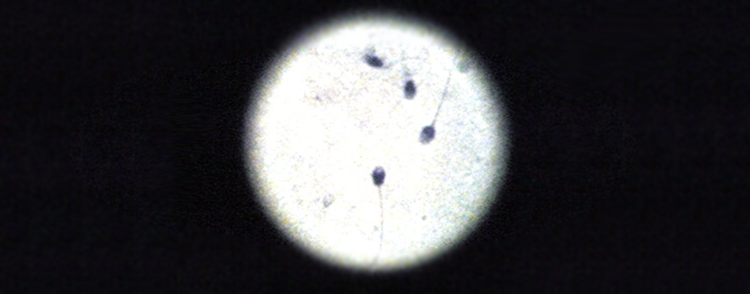

Proprio perché silente, spesso la tricomoniasi viene sottovalutata, anche se è in grado di causare complicanze nelle donne in gravidanza o parti prematuri, infezioni ginecologiche postoperatorie; negli uomini è spesso causa di problemi di motilità degli spermatozoi o sterilità. Se contrato da chi è affetto da HiV, comporta una maggiore facoltà di trasmissione del virus.